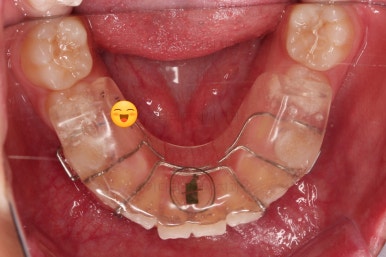

대신 트윈블락은 위아래 어금니를 서로 정교하게 잡아주는 역할을 하지는 않기 때문에 약간 맞물림이 엉성하게 마무리 될 수 있어서 2차교정(치열교정)으로 자연스럽게 넘어가는 경우가 많습니다.

하지만 이번 환자분은 맞물림은 약간 엉성하긴 하지만 2차교정까지는 선택 사항일 정도로 치열 등 나쁘지 않은 모습이었는데요.

그래서 부산소아교정 대신 선택한 옵션이 유지장치 겸 약간의 교합 안정을 목적으로 프링로소를 사용하기로 했습니다.

운동선수 마우스피스 같이 생긴 트윈블락 보다는 훨씬 말랑한 재질이며 착용시간도 더 짧은 장치입니다.

그러면 트윈블락 보다 더 좋은거 아니냐? 생각하실 수 있지만 약간 적용할 수 있는 케이스가 다르기 때문에 전문가와 상의를 통한 신중한 판단이 중요합니다.